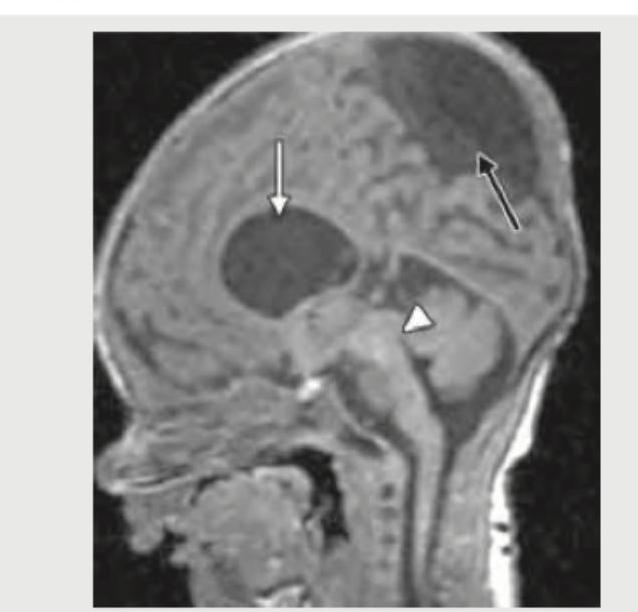

The MRI head of this infant with macrocephaly shows which of the following?

Explanation: ***Dandy-Walker syndrome*** - The MRI image clearly shows a **large posterior fossa cyst** (dilated fourth ventricle, indicated by the white arrow on top) communicating with the fourth ventricle and **agenesis/hypoplasia of the cerebellar vermis** (indicated by the white arrowhead). These are the classic features of Dandy-Walker syndrome. - The presence of **macrocephaly** in the infant is consistent with the obstructive hydrocephalus often associated with Dandy-Walker malformation, due to impaired CSF flow from the dilated fourth ventricle. *Aqueductal stenosis* - Aqueductal stenosis would primarily cause **dilatation of the lateral and third ventricles**, with a normal-sized fourth ventricle. - It would not typically present with a large posterior fossa cyst or cerebellar vermis hypoplasia/agenesis. *Tubercular meningitis* - Tubercular meningitis usually presents with **basilar meningeal enhancement** and sometimes hydrocephalus, but not with severe structural malformations of the cerebellum and fourth ventricle as seen here. - Imaging findings would include basal exudates, infarctions, and occasionally tuberculomas. *Neurocysticercosis* - Neurocysticercosis causes **cysts within the brain parenchyma** (often with an eccentric scolex) or within the ventricular system, typically in older children or adults from endemic areas. - It does not cause the characteristic posterior fossa malformation with vermian agenesis and communication with the fourth ventricle seen in the image.